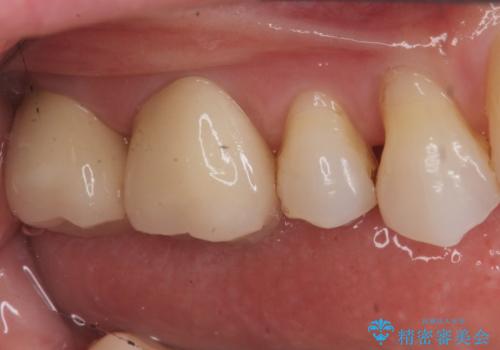

銀歯を白くしたい セラミッククラウンでの治療

- 銀歯を白くしたいとのことで来院されました。

銀の詰め物を除去した後、その奥にある古い詰め物も除去し完全にむし歯を取り切ったことを確認してからセラミッククラウンを装着していきます。